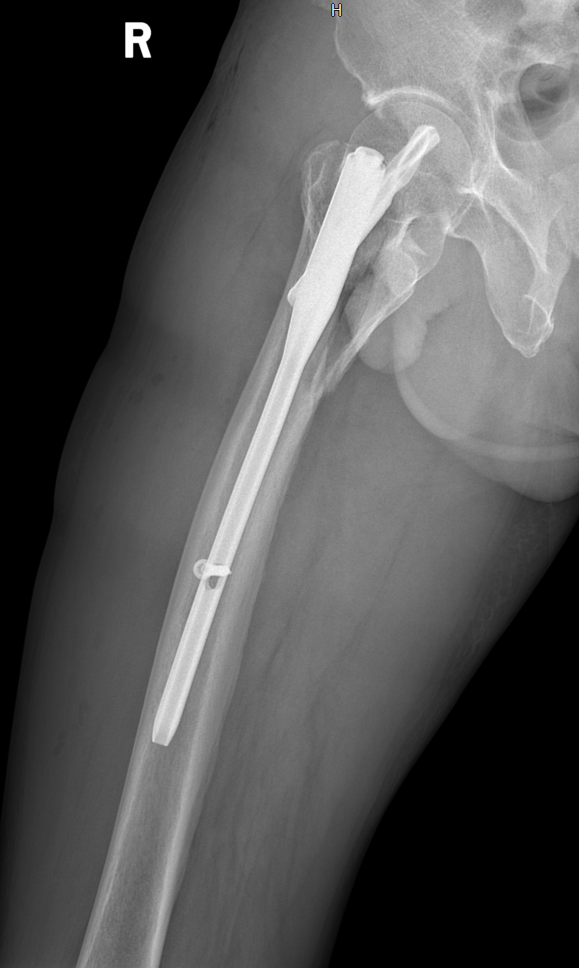

排除手术禁忌症后,于我院在“椎管内麻醉”下行“右侧股骨转子间骨折闭合复位髓内钉内固定术”,术后安返病房,行抗炎、消肿、止痛等积极对症治疗。

术后影像学检查: